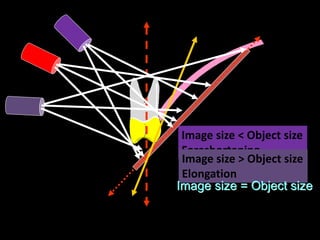

2. The paralleling cone technique provides accurate images with little magnification and no superimposition but is more difficult for patients. The bisecting angle technique is easier for patients but results in more image distortion.